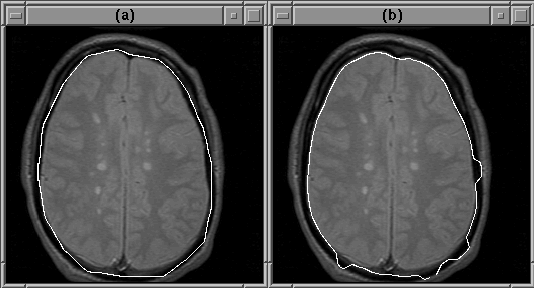

Figure 5.10 shows a case where the igraph of Figure 5.8 fails even though the initial contour provided by the user is reasonable. In this case the deformable contour attached itself to the wrong edge.

Figure 5.10: The active contour model can fail to detect the intracranial boundary. The contour attaches itself to the edge of another feature instead. (a) The initial guess. (b) The converged contour.

As mentioned previously, this problem can be remedied by incorporating the gradient direction into the active contour model algorithm. Figure 5.11 shows the igraph of Figure 5.8 modified to use gradient direction. The active contour model operator, mriSnakes2D2, utilizes both gradient direction and balloon forces.

Given the same initial guess as that in Figure 5.10, and with balloon forces disabled, mriSnakes2D2 produced better results than mriSnakes2D. Figure 5.12 shows that the correct edges are found.

Figure 5.12: The deformable contour attaches itself to the edge of the intracranial boundary because the edges of the other features run in the wrong directions. (a) The initial guess. (b) The converged contour.